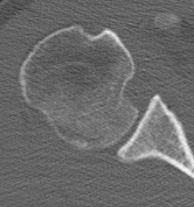

CT scan

Confirms dislocation

Reverse Hill Sachs

Humeral head defect

- caused by impaction of anterior humeral head on posterior glenoid

- intra-articular

- measured as a percentage of the articular surface

Lesser tuberosity fractures

Posterior glenoid fractures / bony bankart